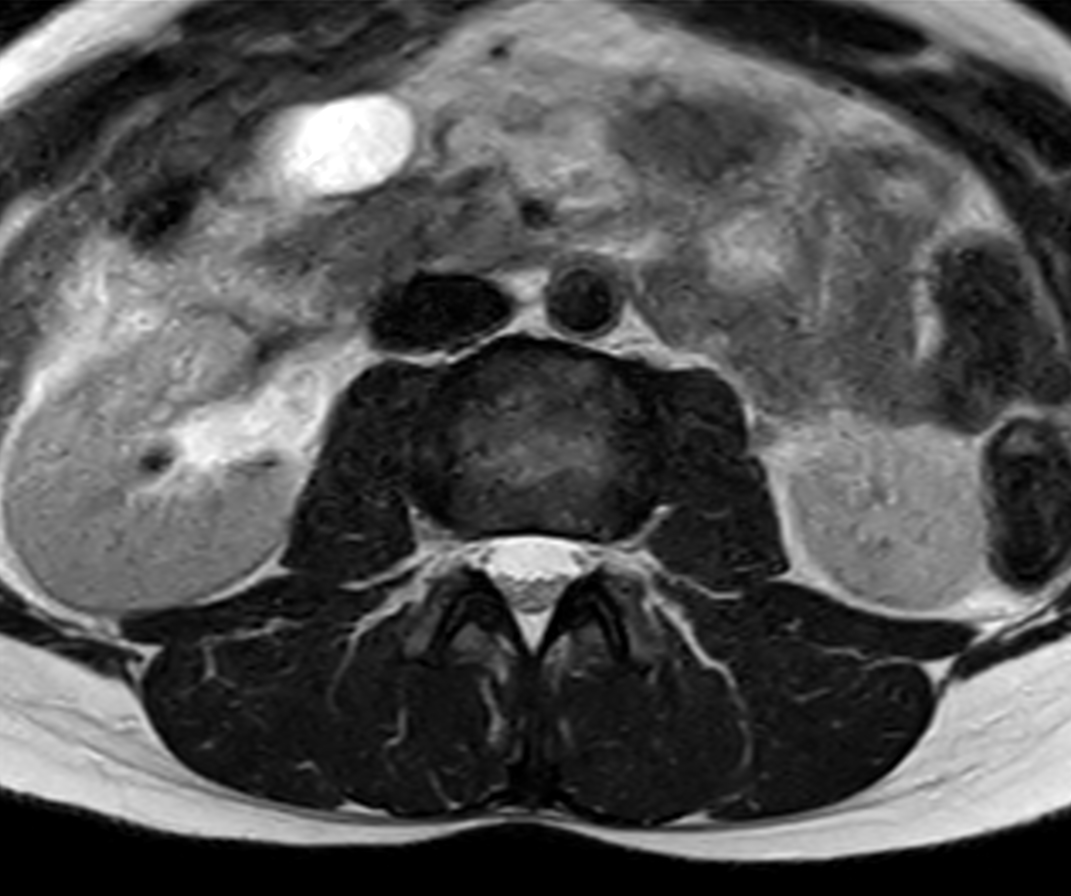

Axial T2w TSE